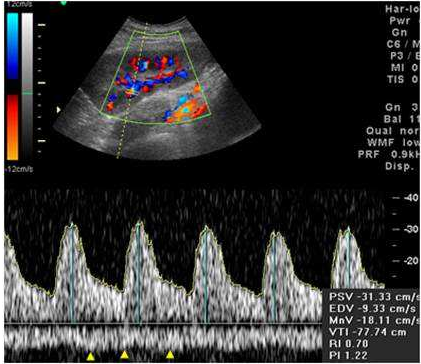

60.85歲男性病人,下肢腫脹。下圖為左側腹股溝血管掃描,則下列選項何者正確? (A)此頻譜代表所掃描為正常股動脈 (B)此頻譜代表所掃描為正常股靜脈 (C)動靜脈瘻管 (D)靜脈阻塞

61.下圖為移植腎之彩色都卜勒超音波圖,下方黃色箭頭所指之頻譜為何? (A)mirror image artifact (B)aliasing artifact (C)正常之腎葉間靜脈(interlobar vein) (D)正常之腎節動脈(segmental artery)